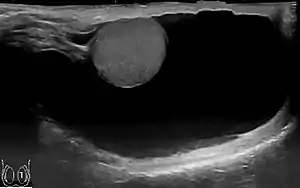

Through diagnostic ultrasound the accumulation of fluids can be diagnosed correctly.